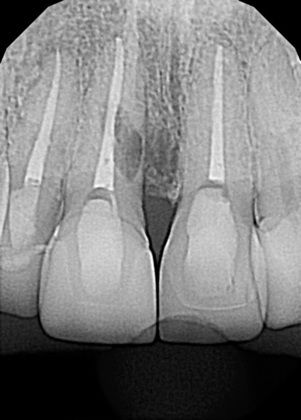

Internal or external resorption of roots is an idiopathic condition affecting teeth in traumatic occlusion. It is a "silent killer" of teeth. We recently completed a case where one tooth had to be replaced with a dental implant and the other required a new dental crown following the exploration of its root for evidence of internal resorption. The Nobel Biocare implant system was used and the patient never went without a tooth. Immediate temporization during the surgery to remove the root was deployed and the patient was not inconvenienced by a removable temporary solution.